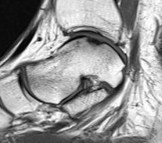

Ankle arthroscopy can be helpful for patients who have damage to the cartilage of the ankle joint. Typically sustained after an ankle sprain, some people who have continued pain may have a small piece of bone and cartilage that is loose inside the ankle joint.

Ankle arthroscopy can be used to remove the loose fragment, and perform surgery to help stimulate the growth of fibrocartilage in the defect. This is done through two small incisions at the front of the ankle. The surgery is very safe, with a very low risk of infection. The main risk is to small sensory nerves around the ankle.